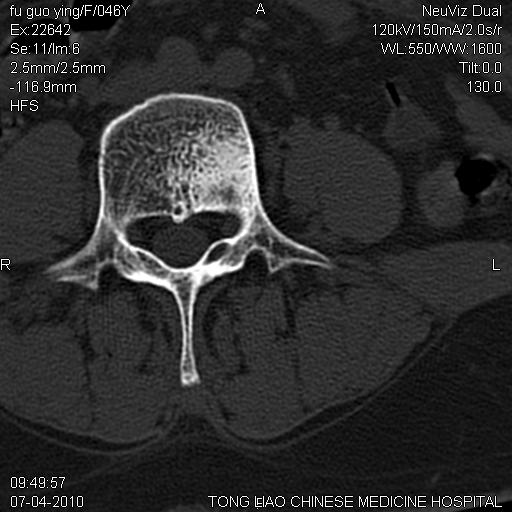

标题: CT27489:患者腰疼,其余椎体未见异常! [打印本页]

标题: CT27489:患者腰疼,其余椎体未见异常!

女性46岁,左髂骨溶骨性破坏+软组织肿块,考虑转移瘤,腰椎为退变/增生硬化/软骨下骨囊变。

不排除多发性骨转移瘤可能;建议行进一步检查。

不排除多发性骨转移瘤可能;建议行进一步检查及查原发灶。